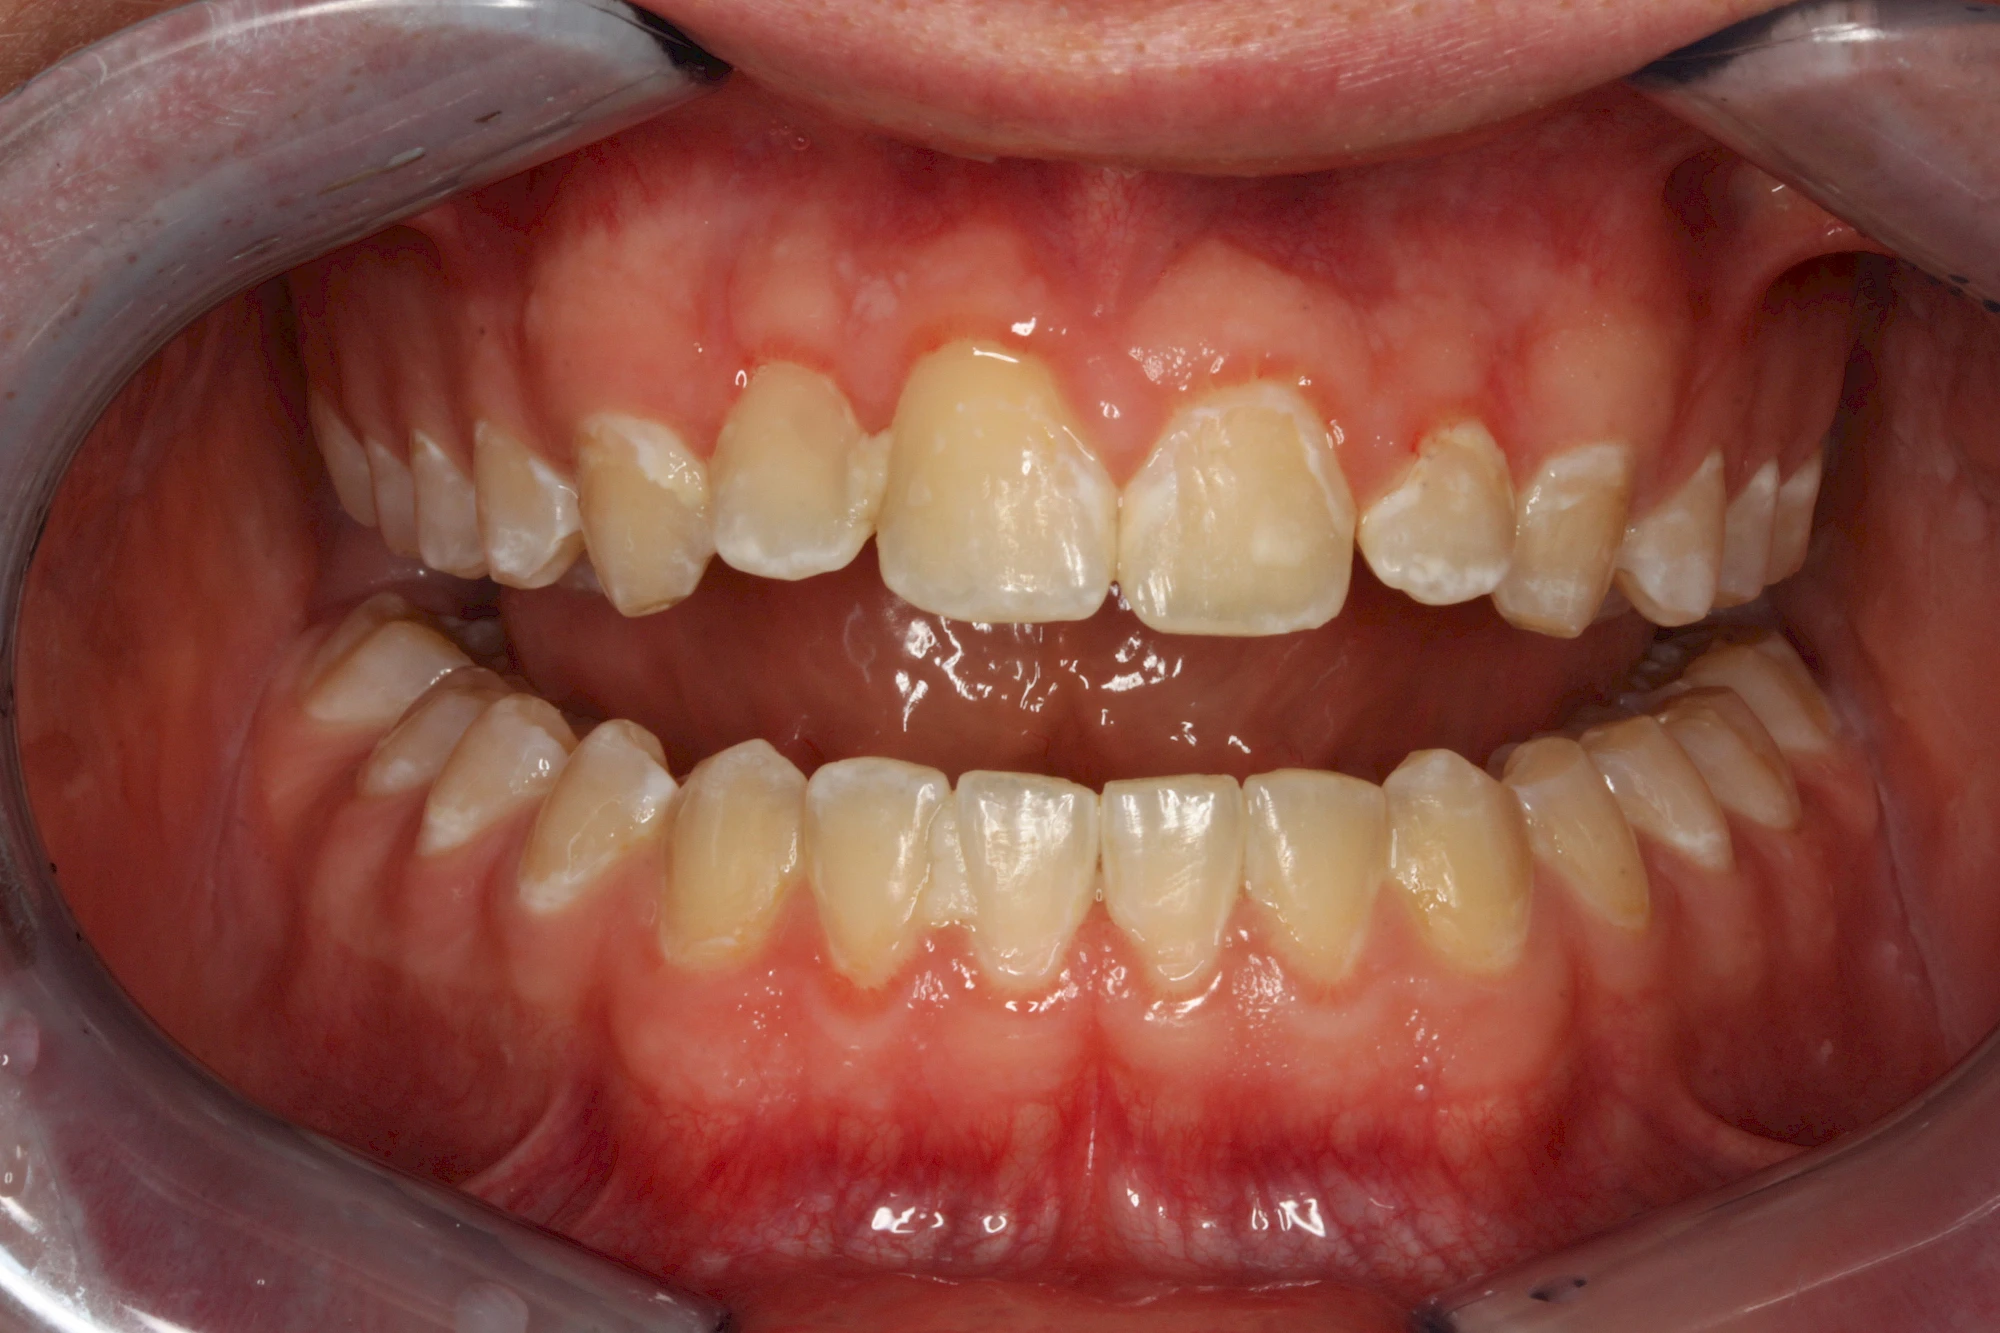

Verfärbungen an Zähnen können außen aufgelagert oder im Zahn eingelagert sein.

Von außen (exogen) eher dunkel gefärbt und meist mehrere Zähne betroffen:

- Genußmittel (Tee, Kaffee, Rauchen)

- Medikamente (z. B. Eisen)